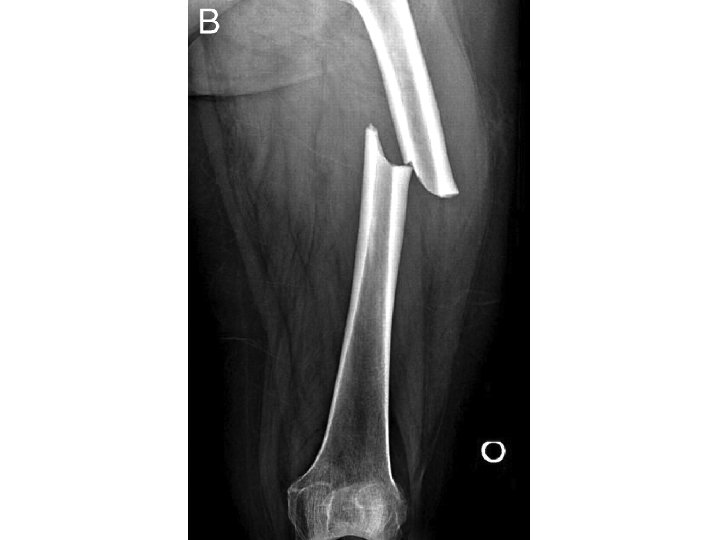

ONE MORE EXAMPLE…

ANS: COMMINUTED FRACTURE • Comminuted fractures are those with 2 or more bone fragments are present • Sometimes difficult to appreciate on x-ray but will clearly show on CT scan • To fully describe the fracture, this is a closed R comminuted intertrochanteric fracture